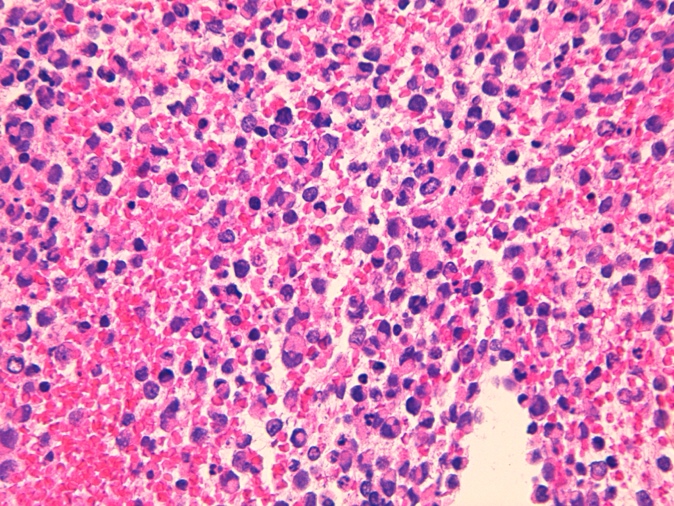

Se deriva paciente a servicio de diagnóstico rápido para completar estudio mediante PAAF-EUS y PAAF de adenopatías (Figura 2). Finalmente se diagnostica de tumor neuroendócrino de páncreas G3, estadío IV: cT3 (20mm, con invasión de grasa perirrenal), cN1 (peripancreáticas y retroperitoneales) y M1 (ganglionar supraclavicular, paraesofágica, retrocrural y ósea ilíaca derecha) por lo que inicia taratamiento por oncología.

Figura 2: Anatomía patológica: Tinción con H-E y Sinaptofisina.